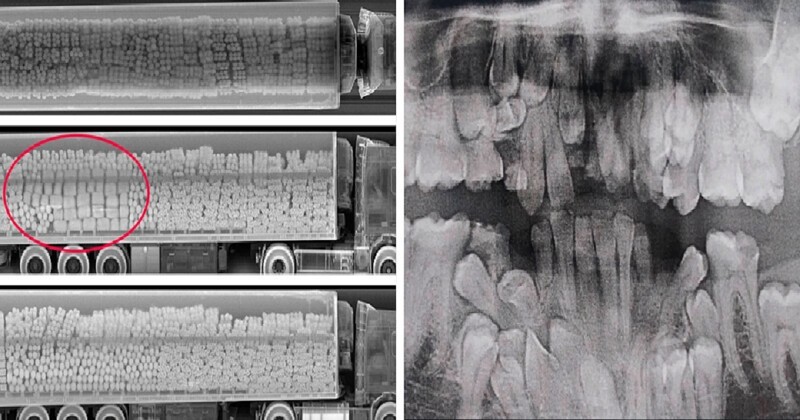

Необычные рентгеновские снимки: то, что скрыто внутри

Раздел: Визуальный дайджест